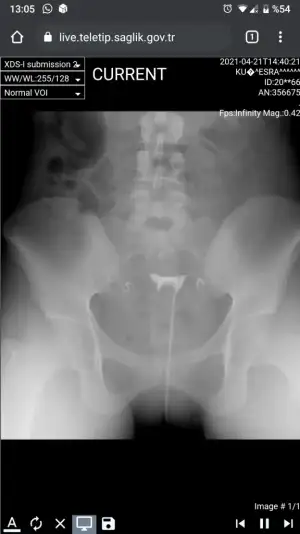

Kızlar benim sonucumuda yorumlayabilir misiniz ben anlamıyorum hiç dün çekildim daha

Eklentiler

• Screenshot_20210422-130549.webp

Screenshot_20210422-130549.webp

16,8 KB · Görüntüleme: 262

Sorun yok gibi duruyor

İki yandaki tüpten de sıvı geçmiş

Yine de en iyi teşhisi doktorun koyacaktır. Geçmiş olsun